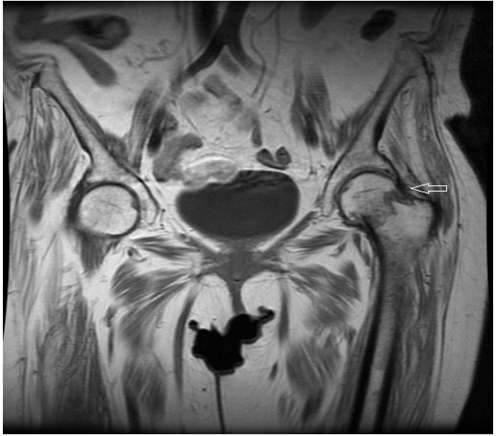

A 72-year-old female had a history of left hip trauma after tripping and falling at home. She was brought immediately to the emergency department and an anterior-posterior hip X-ray was done (Figure 1). As seen in the X-ray there was no sign of fracture but the clinical examination revealed pain at the left hip and limited mobility. Thus, considering the age of the patient, a pelvic CT scan was requested which also revealed no injury to the left hip (Figure 2). The patient was discharged and left home with anti-inflammatory and pain medication, being programmed to return after 7 days for a follow-up.

Figure 1: X-ray at the first presentation showing no fracture.